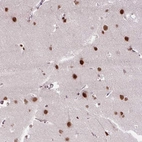

Immunohistochemical staining of human cerebral cortex shows strong nuclear positivity in neuronal cells.